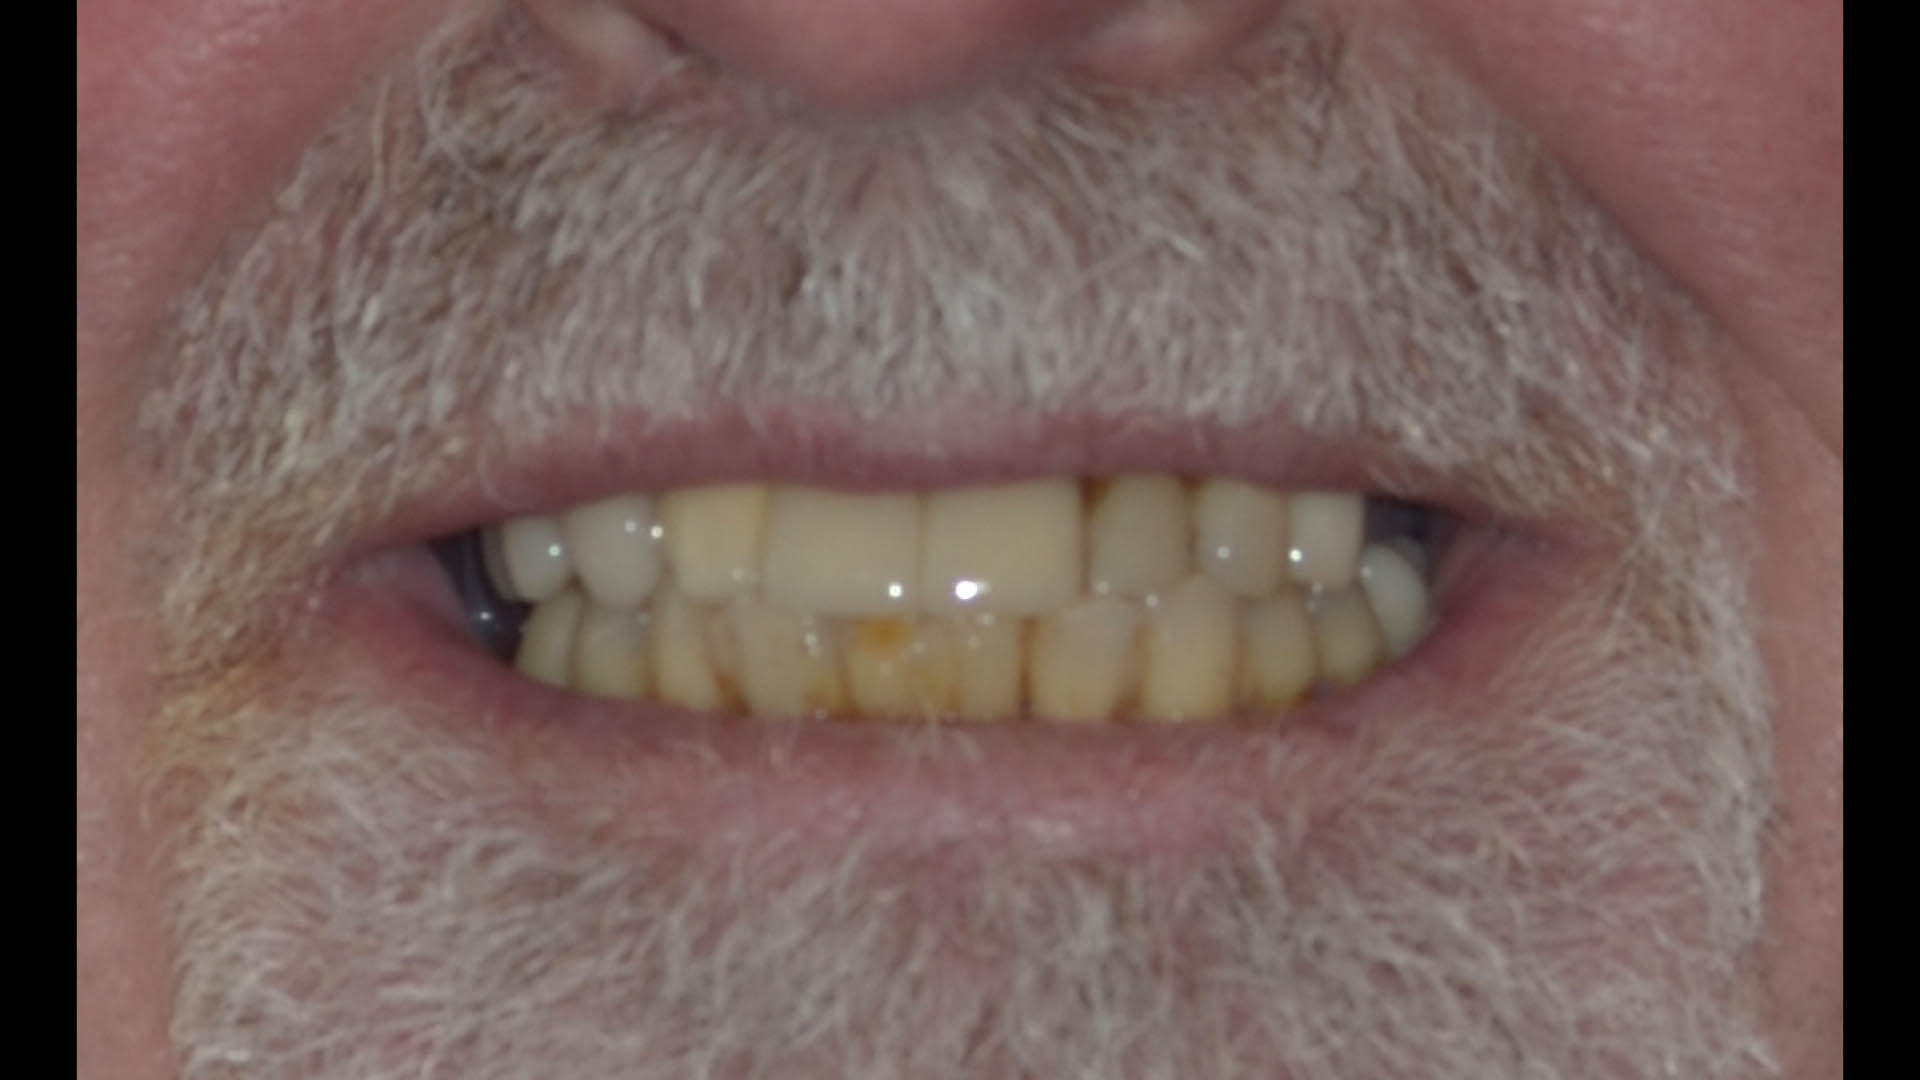

Take a glimpse into the magic of Coral Gables Dentistry through our before and after pictures. See firsthand the incredible smile makeover transformations that have brought confidence and joy to our patients.